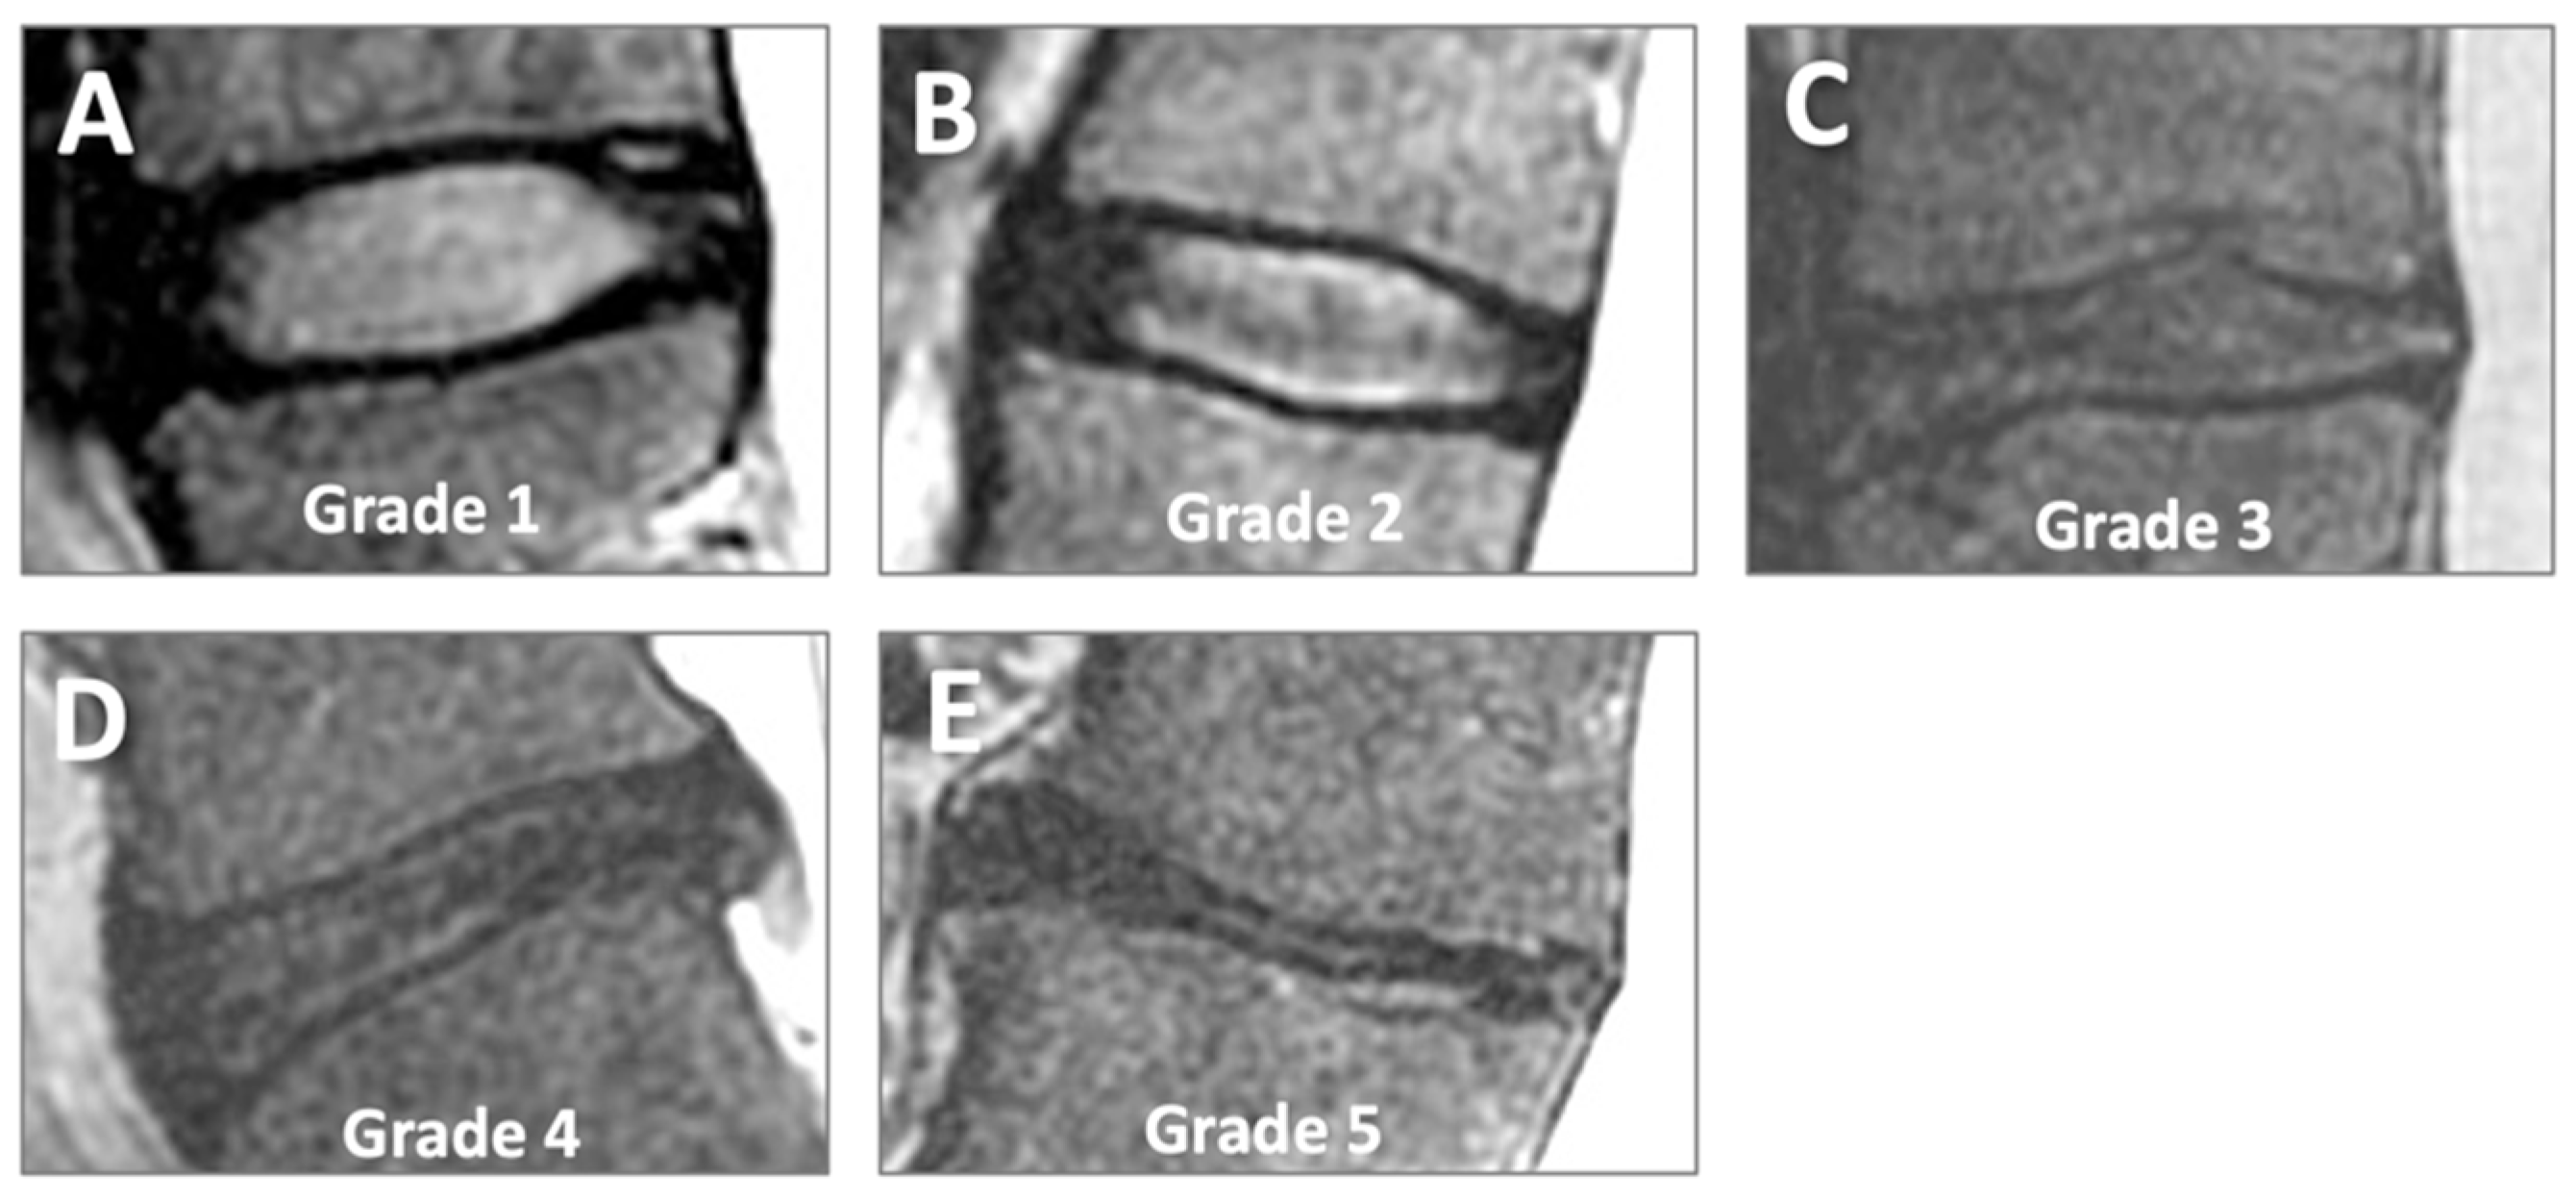

- Pfirrmann, C.W.; Metzdorf, A.; Zanetti, M.; Hodler, J.; Boos, N. Magnetic resonance classification of lumbar intervertebral disc degeneration. Spine 2001, 26, 1873–1878. [Google Scholar] [CrossRef] [PubMed]

| Disc | G1 | G2 | G3 | G4 | G5 |

| Asx | 27.8% | 66.7% | 5.6% | 0% | 0% |

| Sx | 4.6% | 48.1% | 34.3% | 11.1% | 1.9% |